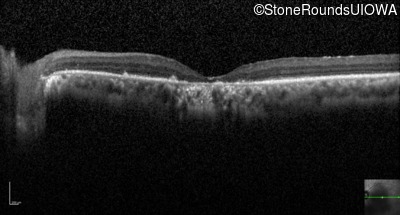

Optical Coherence Tomography - Right - Count Fingers

Exemplar / OCT Stack

Optical Coherence Tomography - Left - Count Fingers